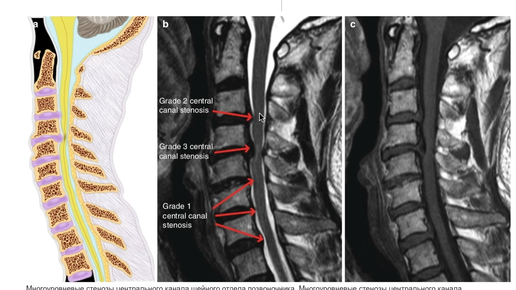

Классификация стенозов шейного отдела позвоночника.